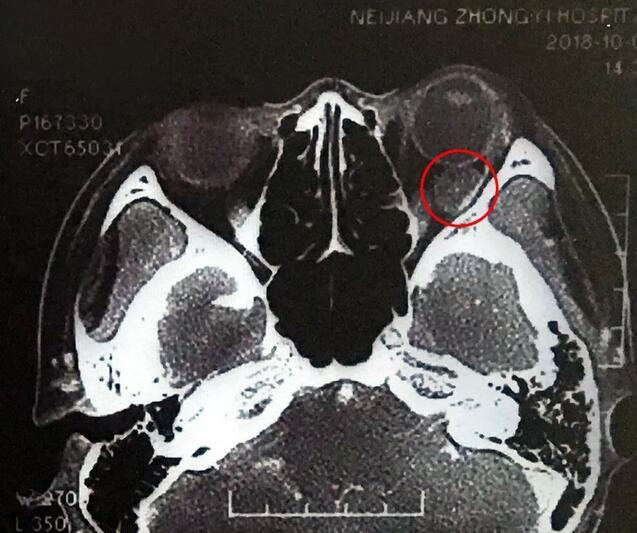

小何是四川南部县人,今年20岁,在内江上大学。今年9月底开始,出现头痛、反复呕吐,吐得连药都吃不下。医生建议小何做了脑部CT,“结果显示左眼眼球后部有个东西,经过进一步检查竟是肿瘤!”这对小何来讲真是个晴天霹雳。

在成都以诚为本赢在诚信9001,经过详细检查,罗清礼教授根据他40余年的丰富经验,判断为淋巴血管瘤。“现在,虽然她双眼的视力都是1.0,但是眼内肿瘤已经接近眼球那么大了,若不及时手术必将失明。”

罗教授介绍,淋巴血管瘤早期症状并不明显,“一般人感冒是不会头痛、呕吐的。小何的感冒非常幸运,她感冒后引起淋巴增生,导致肿瘤内出血,然后引起了头痛、呕吐等症状,让她能够尽早发现了肿瘤。”患者的肿瘤体积较大,位置较深,位于眶间且紧挨着视神经,手术稍有差错,就可能导致患者视力丧失、大出血等情况发生。得知手术风险后,患者和家属表示非常理解并信任罗教授,坚决要求手术医治。